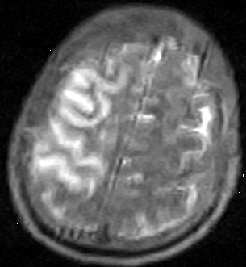

外傷後腦脂肪栓塞CT圖併發症:

外傷後腦脂肪栓塞CT圖鑑別診斷:

在複合性損傷病人,病情平穩或好轉後又出現新的腦部症狀,在考慮到顱內血腫的同時,應想到腦脂肪栓塞的可能。CT掃描有助診斷。

2.CT和MRI掃描 CT掃描及演變規律同腦梗死。但有以下兩特點:

(1)常為出血性梗死。

(2)不同動脈供血區顯示多處皮質區梗死。MRI在T1和T2加權圖像上,均可見腦白質中多數高信號病灶。